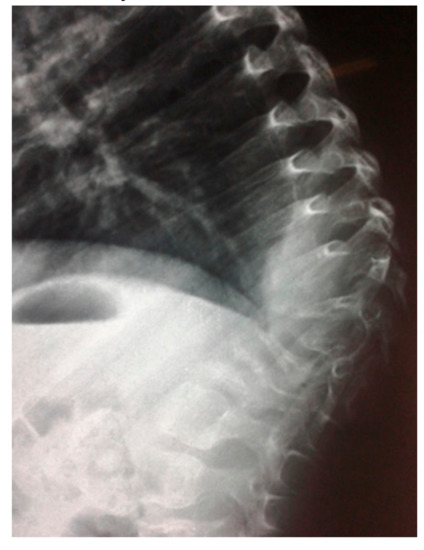

- 3D reconstruction CT scan in a-20-years-old-girl showed severe flattening, fusion, shrinkage and compression of the vanished thoracic spine T3-T9 causing effectively the development of painful kyphoscoliosis. Vanishing bone extended to involve the right shoulder joint resulted in total drop of the right upper limb (Figure 3).